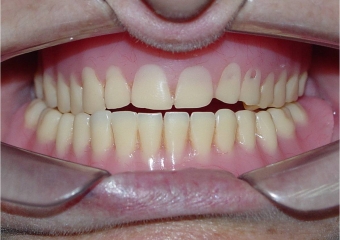

Imagem final

Sorriso final, do caso terminado em setembro de 2013